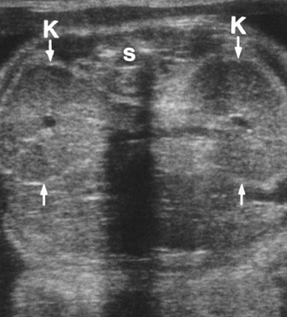

Bilateral kidneys - enlarged (Beckwith weidemann)

IPKD (ARPKD)